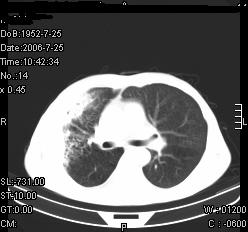

患者,男,54岁,咳嗦,咳痰20天。抗炎治疗2周。现esr76mm/h,目前患者症状明显好转,但发现两次ct片未见明显变化。两次分别做与7.25、7.31。第一次诊断右肺上叶炎症累计胸膜。大家看,从影像上内排除结核吗?

结核的可能性非常大,右上肺病变应该考虑干酪性肺炎。理由:

1.纵隔内多发淋巴结肿大。

2.esr76mm/h。

3.虽经抗炎治疗肺窗病灶有所吸收、减小,但纵隔窗病灶形态、密度、范围无明显变化。如果是单纯的大叶性肺炎,“抗炎治疗2周,目前患者症状明显好转”病灶应该基本消散了,至少也处于吸收消散期,密度变淡、范围变小。同时本病例所示其内的密度不均匀,见多发大小不一空洞样影也不符合大叶性肺炎吸收消散期表现。

病灶特点:片状 索条 结节混杂影,部分融合,密度不均,广泛累及相应胸膜.

临床治疗;二周未吸收.但症状好转.

多考虑:肺结核.